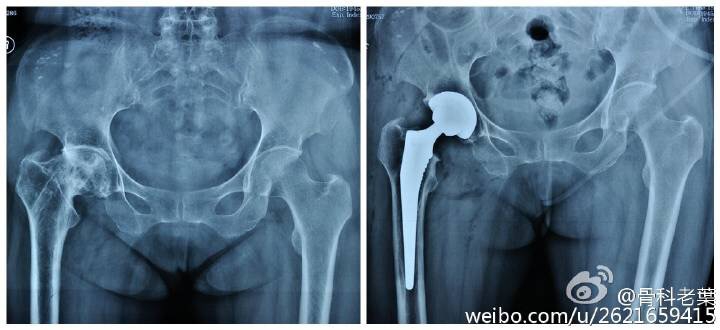

另附典型病例若干: